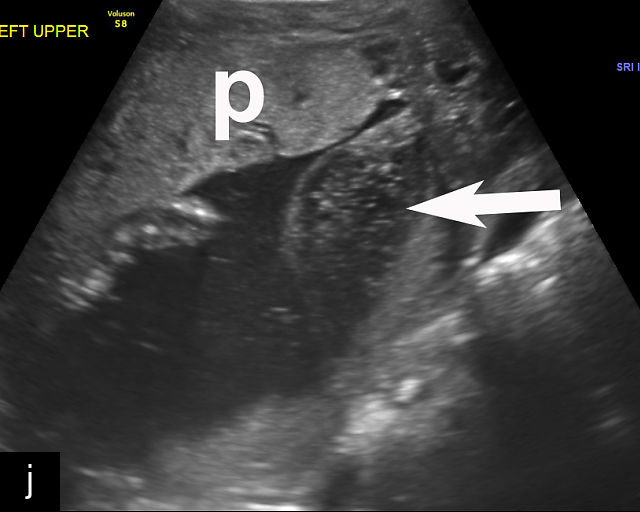

5

Placenta previa and low-lying placenta. (a) Transabdominal grayscale ultrasound image suspicious for placenta previa. The placenta (PL) appears to overlie the internal cervical os (CX). Note the time stamp: 2:19:37. (b) Transvaginal ultrasound of the same patient taken approximately 50 minutes later. Note the time stamp: 3:10:25. The internal os and the lower placental edge are both clearly seen, and the placenta does not overlie the internal os. Because the lower placental edge is 1.93 cm from the internal os, it will likely resolve by the third trimester. (c) Transabdominal grayscale ultrasound of placenta previa. The placenta (p) covers the cervix, but the cervix, especially the internal os, cannot be visualized due to shadowing. (d) Transabdominal grayscale ultrasound of placenta previa. The placenta (p) covers the cervix (c) but shadowing obscures adequate visualization. The internal os is indicated by the arrow. (e) False-positive image of placenta previa on transabdominal grayscale ultrasound. The bladder (b) is full, pushing the anterior and posterior walls of the lower uterine segment (ls) together making it appear that the placenta (p) overlies the internal os of the cervix. In reality, the line depicted by the arrowheads is where the anterior and posterior walls of the lower segment are in proximity to each other. The cervix is much lower and is obscured by shadowing (c). (f) Transabdominal grayscale ultrasound image of placenta previa. The placenta (p) covers the cervix (c), but the cervix, especially the internal os, cannot be visualized due to shadowing. b, bladder. (g) Transvaginal grayscale ultrasound image of placenta previa. The placenta (p) completely covers the internal os (arrow) of the cervix (c). The internal os can be seen clearly. h, fetal head. (h) Transvaginal grayscale ultrasound image of posterior low-lying placenta (p). The lower placental edge is clearly seen and is 1.56 cm from the internal os (arrow) of the cervix (c). The placental edge and the internal os are clearly seen. h, fetal head. (i) Transvaginal grayscale ultrasound image of a posterior placenta previa (p). The internal cervical os is clearly seen (arrow). c, cervix. (j) Transvaginal grayscale ultrasound image of an anterior placenta previa (p). The internal cervical os is clearly seen (arrow). c, cervix; h, fetal head. (k) Transvaginal grayscale ultrasound image of a posterior placenta that was thought to be low-lying on transabdominal sonography but could not be adequately assessed. This examination clearly shows the lower edge of the placenta (p) to be 2.18 cm from the internal os (arrow) of the cervix, firmly establishing that the placenta is not low-lying and allowing the patient to undergo labor safely and deliver vaginally. c, cervix. (l) Transvaginal grayscale ultrasound image of placenta previa. The placenta (p) completely covers the internal os (arrow) of the cervix (c). The internal os can be seen clearly.

This distinction is critical in determining the mode of delivery.49,51 All patients with placenta previa persisting into late pregnancy require cesarean delivery to avoid complications such as severe bleeding.50,60,61 Studies suggest that patients with a lower placental edge located more than 1 cm from the internal os may safely attempt a vaginal delivery without a significant increase in bleeding risk.68,69,70,71

Most cases of placenta previa will be suspected prenatally by transabdominal ultrasound.49 However, this approach has several limitations and may be inaccurate.72,73,74 because the relationship between the placenta and the internal cervical os may be difficult to assess by transabdominal ultrasound.72,73,74 The bladder may be full, pushing the anterior and posterior walls of the lower uterine segment together, falsely creating the impression of a placenta previa (Figure 5e).61 There may be considerable shadowing, including by the fetal presenting part, which may limit the accuracy of transabdominal ultrasound (Figure 5d,f).75 Posterior placentas may be more difficult to assess.

Transvaginal ultrasound overcomes these limitations (Figure 5g–l).72,73,74,76 The probe is inserted into the vagina and therefore is closer to the region of interest.51,61 In addition, transvaginal transducers have higher frequencies and superior resolution compared to transabdominal transducers. Transvaginal ultrasound is safe and is not associated with increased bleeding.72,73,74,75,76 As such, transvaginal ultrasound should be the imaging modality of choice whenever there is suspicion of placenta previa.49,67,77